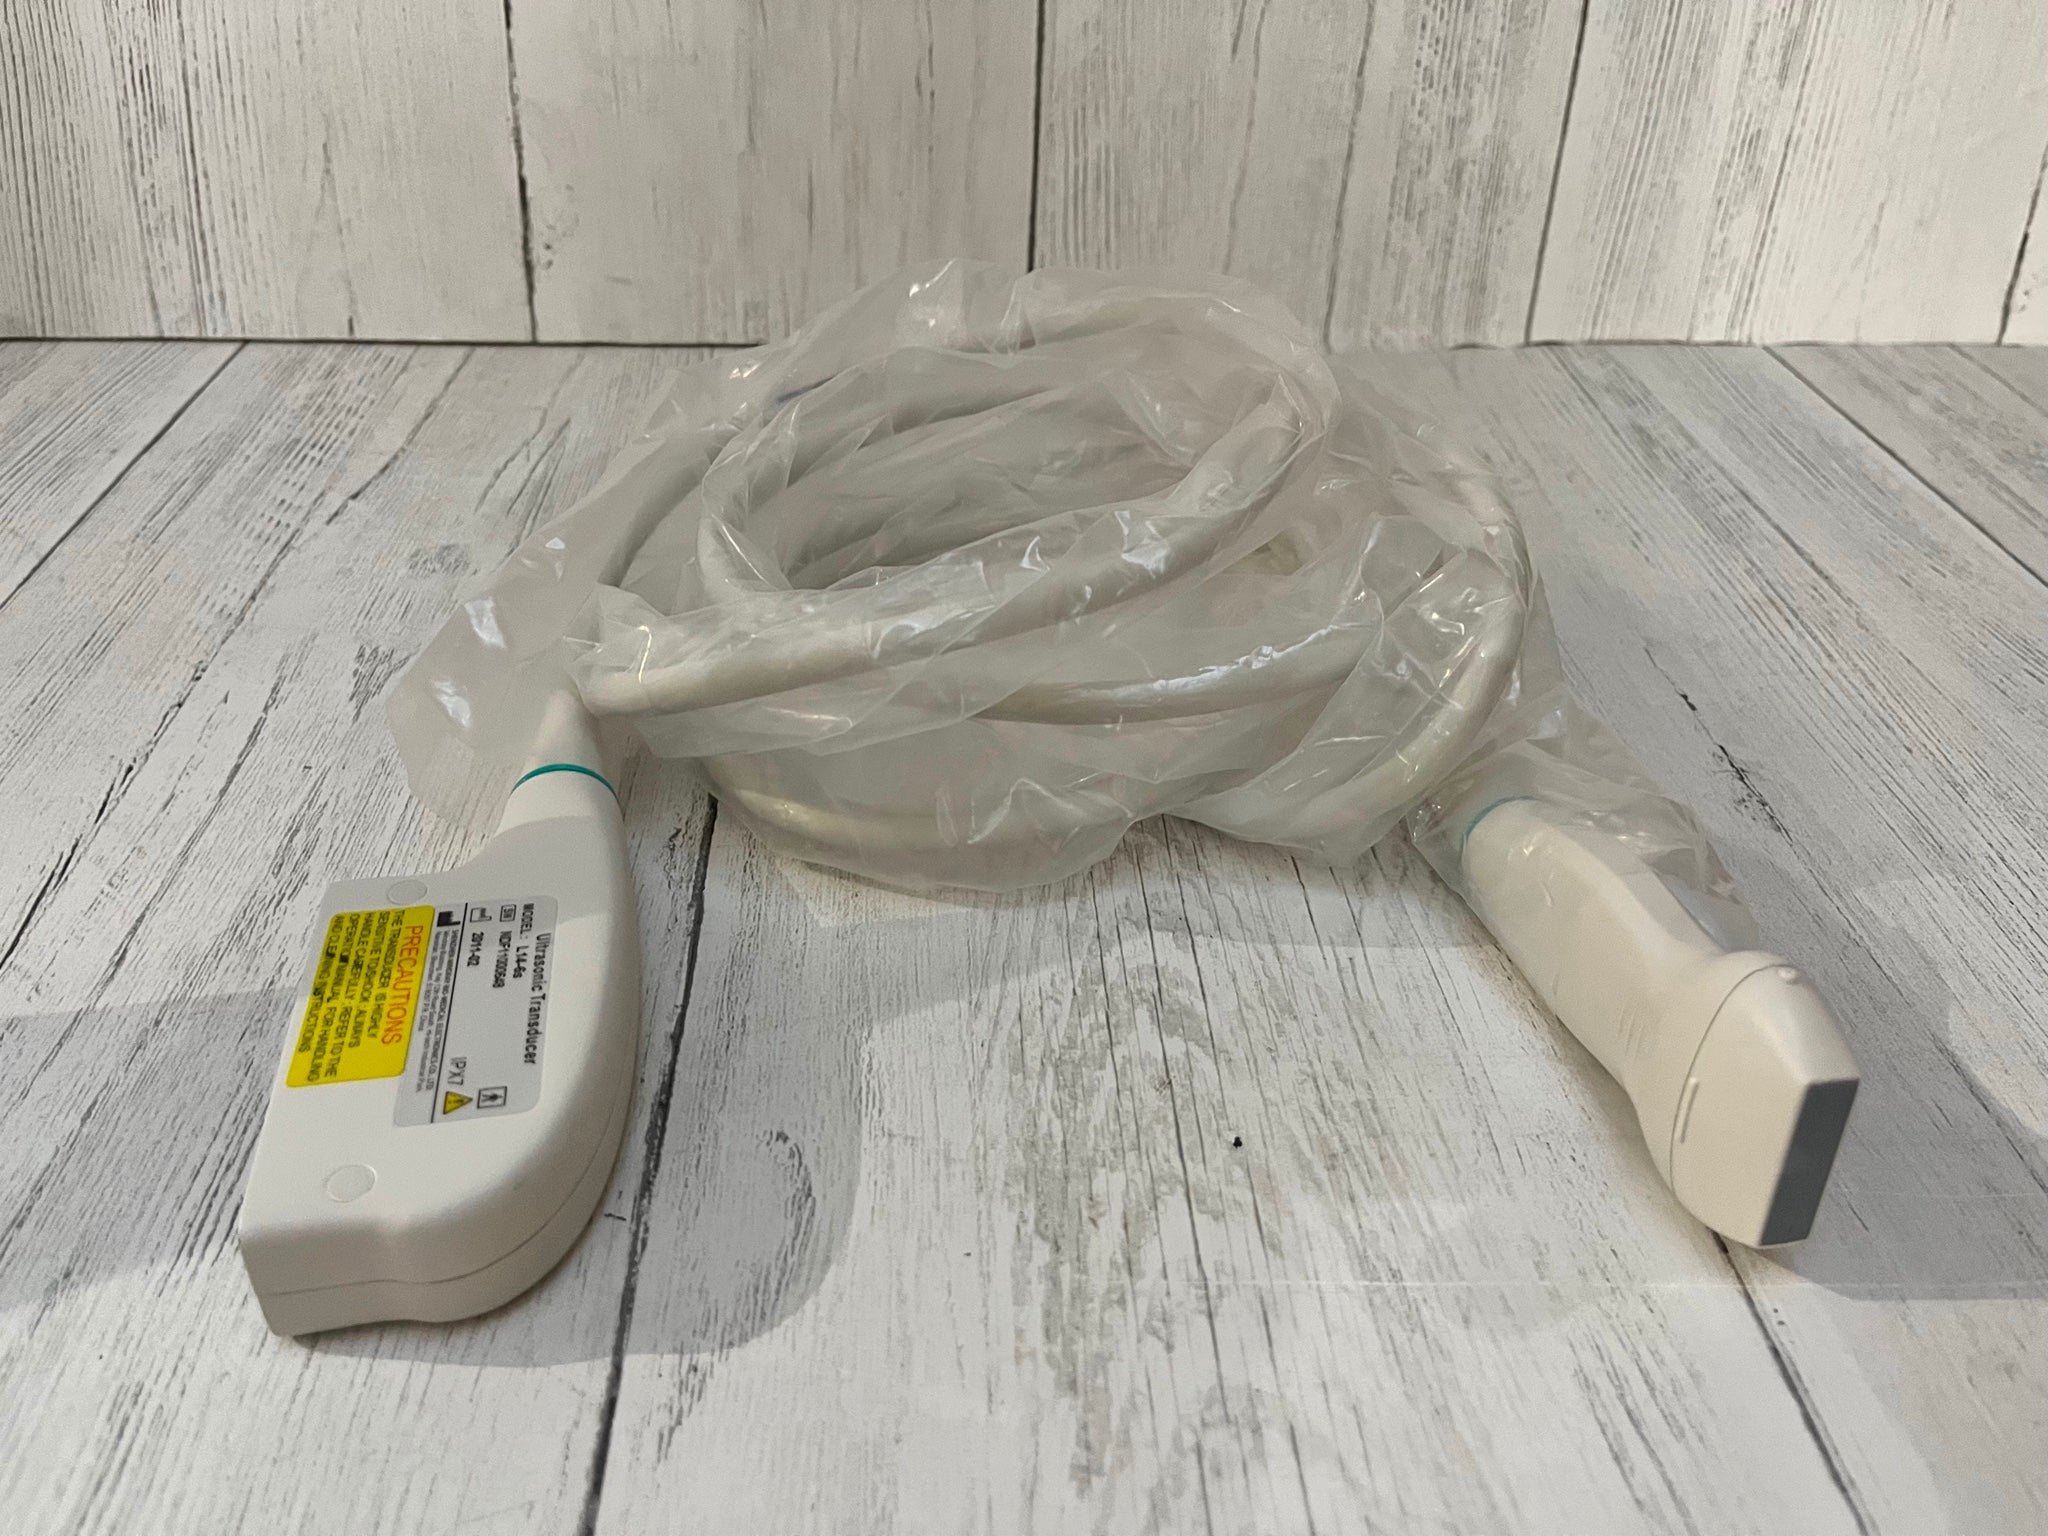

One of the standout features of the TFT LCD Digital Laptop Linear Array Ultrasound Scanner is its linear array probe. This probe is known for its high-frequency linear transducer, which is ideal for scanning small and superficial structures like tendons, arteries, and veins, so it offers precise imaging capabilities. The linear array also supports a range of applications such as musculoskeletal, emergency medicine, and vascular imaging.

Versatility is another key advantage of this ultrasound scanner. It supports a variety of probes that allow for different types of examinations. In particular, the cavity probe included with this machine is useful for gynecological and obstetric purposes. Because this adds another layer of functionality to the device, healthcare providers can deliver comprehensive care using a single machine. With multiple probe options, you can seamlessly switch from one type of imaging to another without missing a beat.